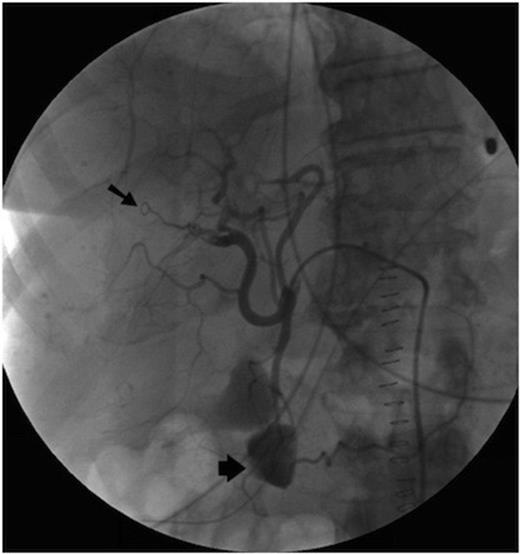

Post operatively the upper gastrointestinal bleeding continued. A second urgent OGD endoscopy showed more blood clots and fresh blood in the fundus, but once again no source for the bleeding was seen. Once the patient was stabilised an angiogram was performed. This showed a 1cm pseudoaneurysm of the right hepatic artery in the right lobe close to the Porta Hepatis. The pseudoaneurysm arose from the anterior branch of the right hepatic artery and communicated with the bile duct. The 2nd part of the duodenum was opacified, showing haemorrhage from the lesion into the duodenum via the bile duct (Figure 1).

Initially, selective embolisation of the anterior right hepatic artery was performed using small coils (COOK UK) and small particles of grated gelatin sponge soaked in 0.5ml of 5% Ethanolamine. However this proved to be ineffective (Figure 2), and so the posterior branch of the right hepatic artery was embolised, successfully controlling the haemobilia. The left hepatic artery was spared.

Following the procedure there were signs of recurrent haemorrhage such as fluctuating serum haemoglobin levels and some ongoing malaena. However, these ceased spontaneously after a few days, and the patient subsequently made an uneventful recovery.